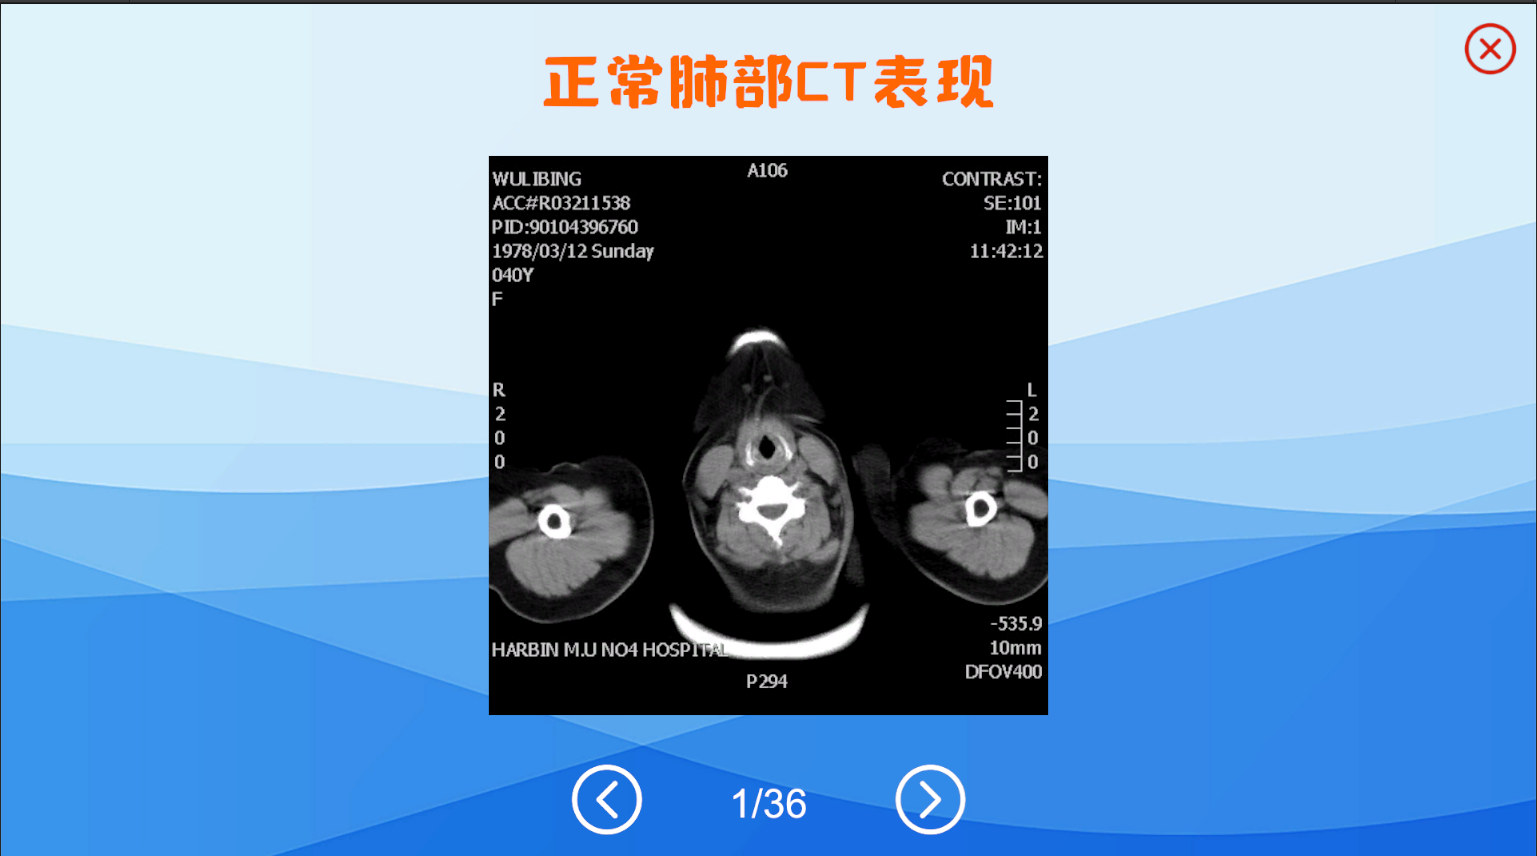

功能集成,目前包括人体解剖学教学、组织学胚胎学教学、介入手术教学、影像学教学等功能

影像数据来源于临床,定制病例模型基于开源软件3DSlicer

本产品打破以往产品功能单一的局面,目前具有解剖教学、组胚教学、影像教学、模拟介入手术等功能

影像学模块模拟PAC系统,在这里您可以学习到各种疾病的影像学表现

基于DICOM影像数据生成病例模型,这里您可以体会介入手术的方式

以下是产品内截图实况